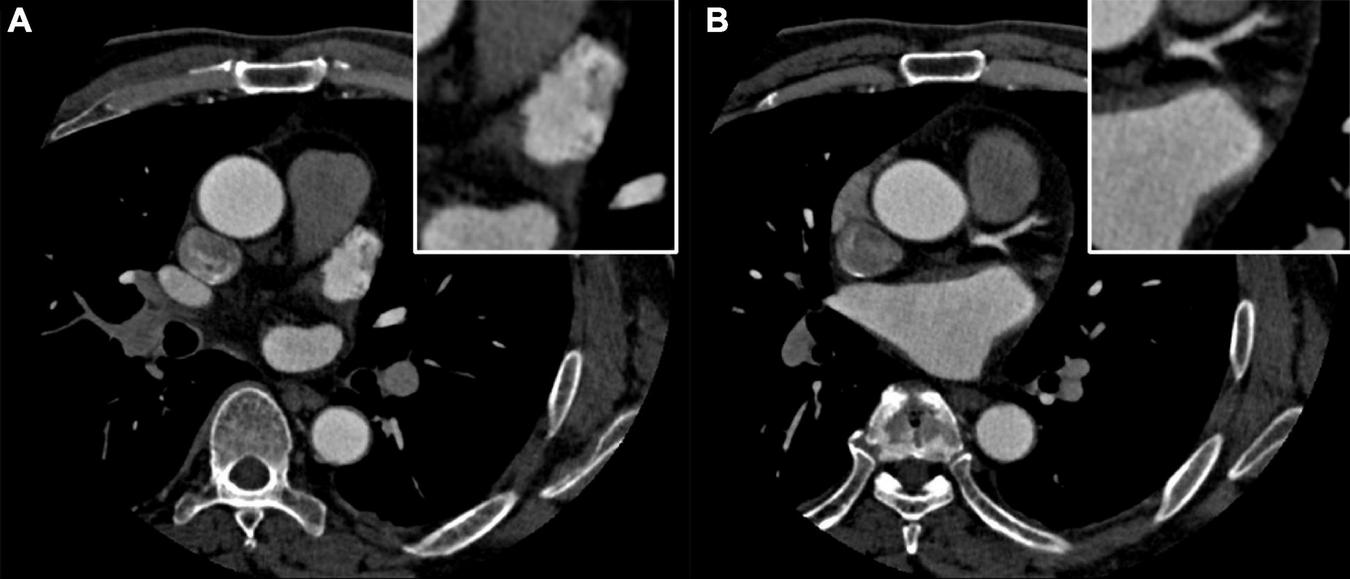

A 58-year-old man was admitted to the cardiovascular department due to palpitation and shortness of breath. He was diagnosed with paroxysmal atrial fibrillation 3 years ago, and no treatment is given. Recent ECG and Holter monitoring confirmed its persistent episode. After being anticoagulated (rivaroxaban 20 mg daily) for 3 weeks, he was admitted and prepared for AF catheter ablation. He had a history of well-controlled hypertension. Physical examination and ECG confirmed the diagnosis of persistent AF. All blood tests and echocardiography were within normal limits, and preoperative left atrium CT angiography demonstrated no intracardiac thrombus (Figures 1A,B).

FIGURE 1

(A,B) Preoperative left atrium computed tomography (CT) angiography excludes the intracardiac thrombus.